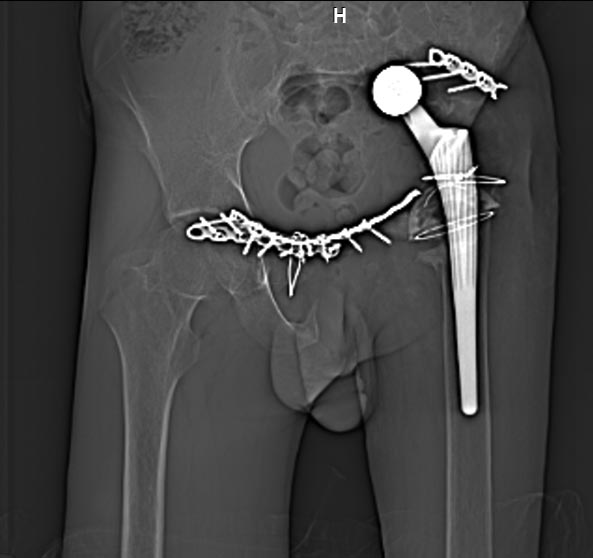

Мужчина 21 год, 2 года назад обнаружен эхиннокок костей таза, часть костей удалена сделано эндопротезирование и остеосинтез. Послеоперациооный период протекал гладко, через 6 месяцев упал, лечился консервативно, далее цепная реакция из проблем: гнойный остеомилит, свищи и лизис костей таза, на бак посеве эхинокок не обнаружен. Бедро не опорно, но больной предвигается на костылях. Картина маслом на рентгене и кт.об артродезировании думали, но диастаз большой, да и на фоне лизиса и остеопороза?????